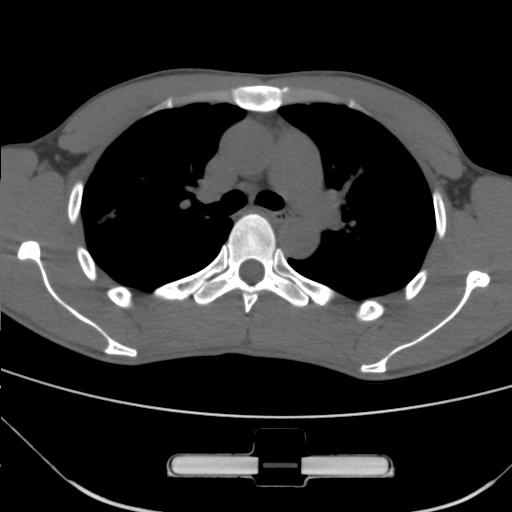

车祸伤者

右肺上叶后段近胸膜下结节样异常密度灶,似见分页及毛刺,考虑右肺上叶周围型肺ca,建议穿刺病理检查

周围型肺ca与炎性假瘤待鉴别。建议穿刺病理检查

缺乏病史,症状体征,但这个孤立结节具备了几乎所有的恶性征象:分叶,毛刺,空泡征,胸膜凹陷征,血管集束。